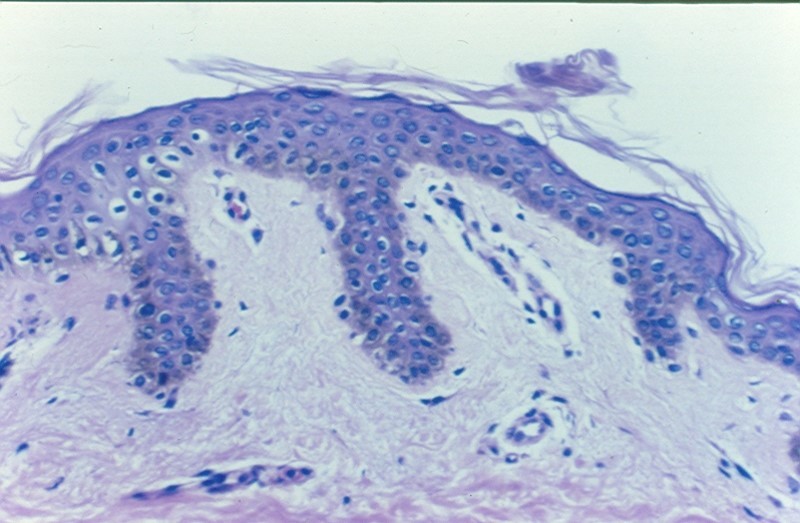

Seborrheic keratosis

dark keratin-filled surface plugs (inset)

benign basaloid cells

prominent keratin-filled “horn” cysts, some of which communicate with the surface (pseudo-horn cysts).